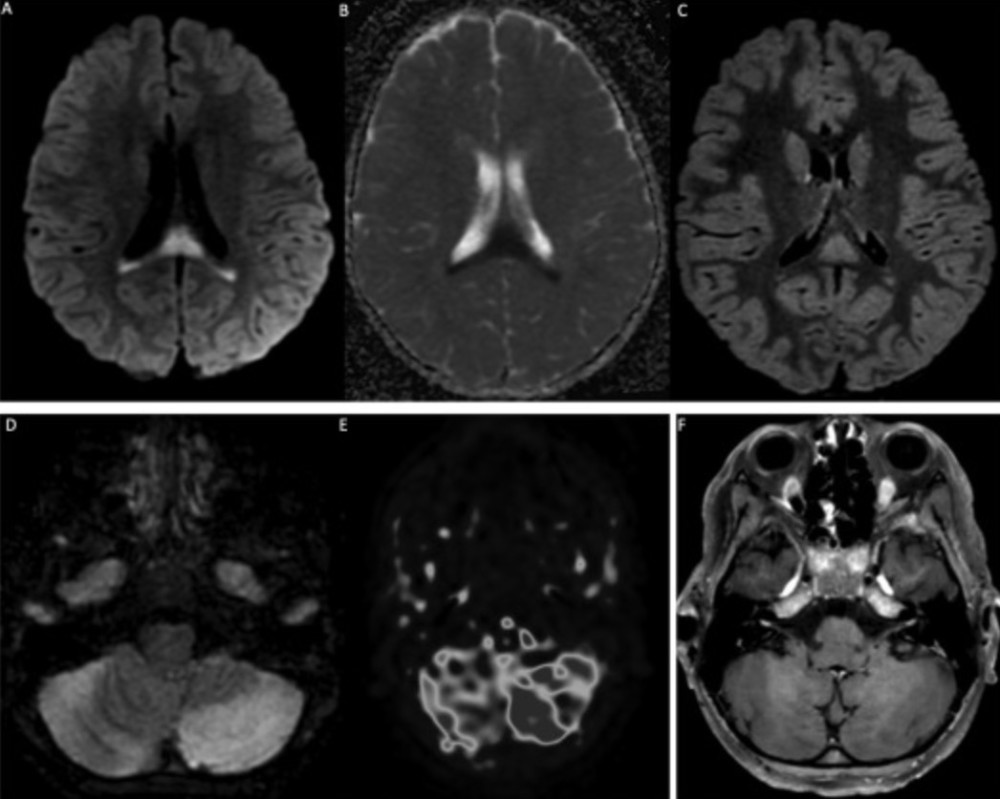

其中6名儿童出现MIS-C,10名儿童出现小脑症状(共济失调、头晕),9名认知功能受损或意识改变。其他零星症状是视力丧失、感觉异常或感觉过敏、括约肌障碍或面瘫。研究者在神经系统症状发作后的中位时间为8天(0至17天)对所有患者进行脑脊液常规检验(CSF)。

19名儿童中有11名出现多细胞增多症(中位数23白细胞/μL,最大300,以淋巴细胞或中性粒细胞为主)。单核细胞增生李斯特菌PCR、巨细胞病毒、肠道病毒、单纯疱疹病毒1和2、人疱疹病毒6、副胆囊病毒和水痘-带状疱疹病毒在所有儿童的脑脊液中均为阴性。19例患者中只有1例脑脊液常规检验出现蛋白升高,≥50mg/dL。在10名测试患者中的2名患者中鉴定出脑脊液寡克隆区带(判断鞘内免疫球蛋白合成的金标准)。在对9名患者进行测试时,脑脊液中的干扰素α分泌始终为阴性。在9名患者中测量了脑脊液中的细胞因子(IL1、IL6、IL10、TNF),其中3名患者异常:2名儿童中存在单一的IL6升高(1118和1551pg/ml,正常值200倍);一名儿童的所有3种细胞因子增加≤10倍正常值。

19名患者中有14名MRI异常。4例MRI显示ADEM伴有多灶性脑损伤,1例伴有视神经炎;3例显示胼胝体细胞毒性病变(CLOCC综合征),胼胝体压部扩散受限,T2-FLAIR高信号,2例小脑炎;1例分别显示孤立性视神经炎、孤立性面神经炎和多发性神经炎。19例脊柱MRI中有5例异常:5例显示脊髓炎,其中3例与ADEM相关,1例为孤立性,1例与马尾神经根的对比增强相关。所有脊髓炎病例均显示超过3个椎体受累。

登录/注册后可看大图

10名测试儿童中有4名的血清中抗MOG(髓鞘少突胶质细胞)和抗AQP4(水通道蛋白4)抗体呈阳性。AQP4主要临床意义在于诊断视神经脊髓炎。MOG的糖蛋白是髓鞘膜和少突胶质细胞表面最外层的膜蛋白,是导致多发性硬化(MS)脱髓鞘的关键成分,针对MOG的抗体能够在体内和体外造成脱髓鞘。

一名抗AQP4抗体阳性的女孩14岁,无既往明显病史,她有单独的右眼视觉症状,其他神经系统检查正常,临床诊断为视神经炎,脑部MRI显示视神经炎无脑部或脊柱异常。其他3名抗MOG抗体阳性的儿童分别为1.5岁、4岁和10岁,其中男孩2人。这3例病例均未出现MIS-C症状,二十出现神经系统症状(2人共济失调,1人癫痫发作、意识丧失、面瘫和偏瘫)。其中的第3名患者进入重症监护室。